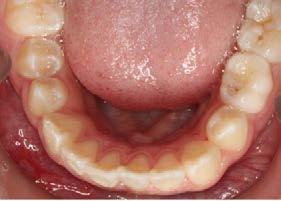

Objetivos: Conseguir clase I canina, controlar el crecimiento vertical, disminuir la convexidad esqueletal, reducir la sobremordida horizontal y mejorar el perfil facial. Caso clínico: Paciente femenina de 9 años, clase II esqueletal, biotipo dolicofacial, perfil convexo, clase II molar, clase II canina y proinclinación de incisivos superiores e inferiores. Resultados: Se logró clase I canina, se controló el crecimiento vertical, se redujo la convexidad esqueletal, se mejoró la sobremordida horizontal y el perfil facial. Conclusiones: El uso combinado de aparatos ortopédicos y aparatología fija en pacientes en crecimiento, junto con un diagnóstico y plan de tratamiento acertado, permite obtener resultados exitosos y estables en la corrección de estas maloclusiones.

La relación maxilomandibular desempeña un papel importante en la posición de los molares y puede clasificarse como clase I, II o III, de acuerdo con la clasificación de Angle. Esqueletalmente, esta relación solo puede determinarse mediante estudios radiológicos; los modelos de estudio solo ofrecen una aproximación clínica.1